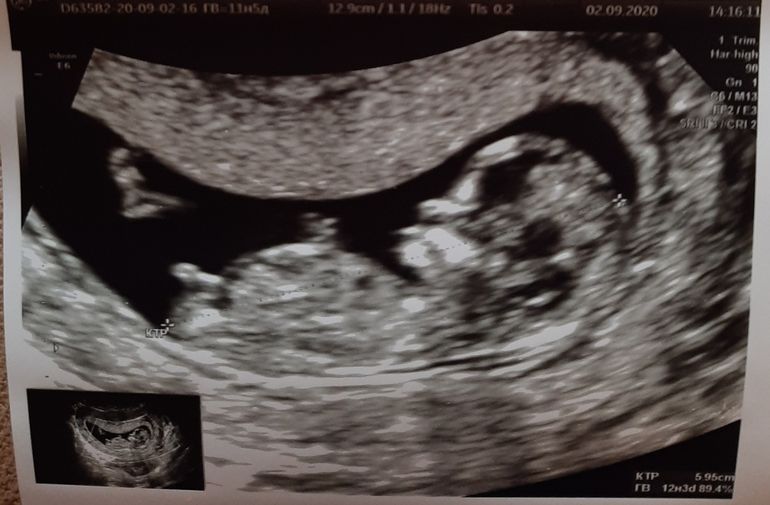

Юлия Sonnце, у меня скрининг был в 11 с чем-то недель, мальчик выглядел так, а в живую (я сама смотрела на экране) я была уверена что 100% девочка, но в 13 недель бугорок поднялся) В общем непонятно)) Изображение

03.12.2022

Здесь видно половой бугорок? Закрасила кружок💙